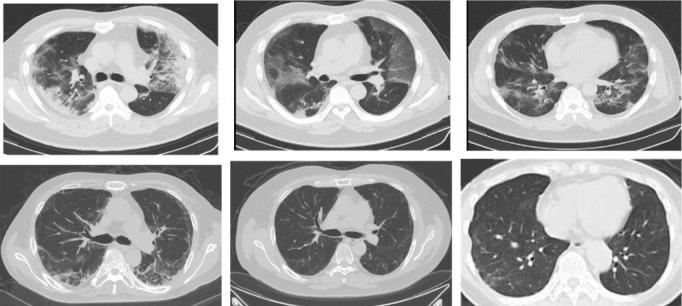

The coronavirus disease, called COVID-19, which is spreading fast worldwide since the end of 2019, and has become a global challenging pandemic. Until 27th May 2020, it caused more than 5.6 million individuals infected throughout the world and resulted in greater than 348,145 deaths. CT images-based classification technique has been tried to use the identification of COVID-19 with CT imaging by hospitals, which aims to minimize the possibility of virus transmission and alleviate the burden of clinicians and radiologists. Early diagnosis of COVID-19, which not only prevents the disease from spreading further but allows more reasonable allocation of limited medical resources. Therefore, CT images play an essential role in identifying cases of COVID-19 that are in great need of intensive clinical care. Unfortunately, the current public health emergency, which has caused great difficulties in collecting a large set of precise data for training neural networks. To tackle this challenge, our first thought is transfer learning, which is a technique that aims to transfer the knowledge from one or more source tasks to a target task when the latter has fewer training data. Since the training data is relatively limited, so a transfer learning-based DensNet-121 approach for the identification of COVID-19 is established. The proposed method is inspired by the precious work of predecessors such as CheXNet for identifying common Pneumonia, which was trained using the large Chest X-ray14 dataset, and the dataset contains 112,120 frontal chest X-rays of 14 different chest diseases (including Pneumonia) that are individually labeled and achieved good performance. Therefore, CheXNet as the pre-trained network was used for the target task (COVID-19 classification) by fine-tuning the network weights on the small-sized dataset in the target task. Finally, we evaluated our proposed method on the COVID-19-CT dataset. Experimentally, our method achieves state-of-the-art performance for the accuracy (ACC) and F1-score. The quantitative indicators show that the proposed method only uses a GPU can reach the best performance, up to 0.87 and 0.86, respectively, compared with some widely used and recent deep learning methods, which are helpful for COVID-19 diagnosis and patient triage. The codes used in this manuscript are publicly available on GitHub at (https://github.com/lichun0503/CT-Classification).